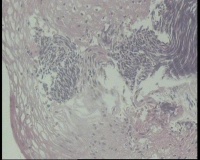

镜下见鳞状上皮大部分如(图1) ,仅局灶鳞状上皮异型(图2-4),细胞似牵拉变形,部分腺腔内见异型细胞团,这些细胞跟LEEP刀手术电凝有关系吗?这个怎么报?累腺明显,上皮图1怎么报?能报CINII—III累及腺体吗?还是宫颈高级别鳞状上皮内病变累及腺体

图2